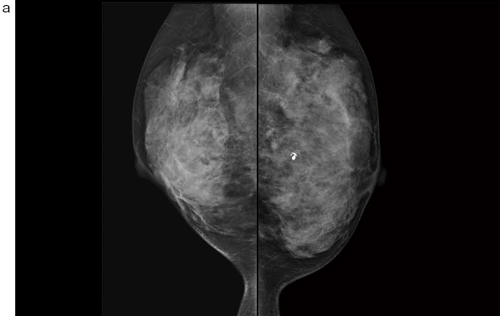

■症例1:40歳代後半,女性。両側乳房腫瘤を自覚,近医で良性と診断。超音波フォロー中に新規病変を指摘されて当院へ紹介。

a:左右MLO画像